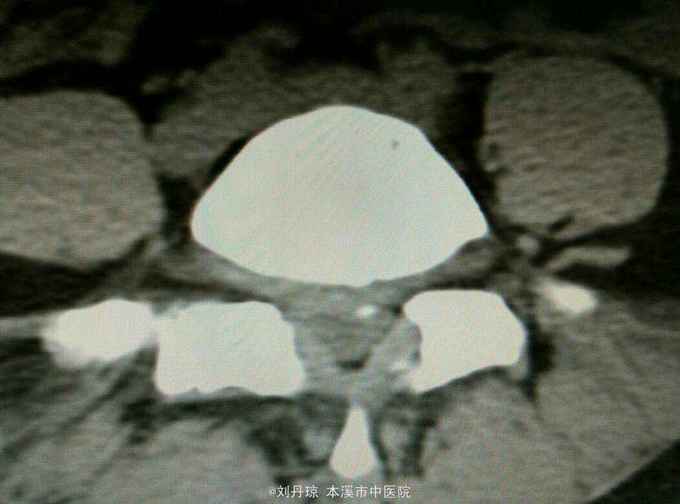

腰部疼痛伴右下肢放射痛麻木感1年,加重1月。患者1年前劳累后感到腰部疼痛伴右下肢放射痛麻木感,近1月病情加重来诊。

查体:L3—S1棘突右旁压痛阳性。直腿抬高实验左70度,右40度。 直腿抬高加强实验左侧阴性,右侧阳性。腰椎功能障碍。 辅查:CT: L3—S1椎间盘突出。